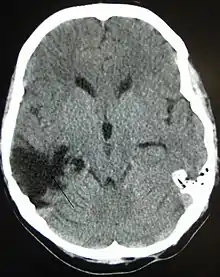

A CT of the head years after a traumatic brain injury showing an empty space where the damage occurred, marked by the arrow

There are several imaging techniques that can aid in diagnosing and assessing the extent of brain damage, such as computed tomography (CT) scan, magnetic resonance imaging (MRI), diffusion tensor imaging (DTI) magnetic resonance spectroscopy (MRS), positron emission tomography (PET), and single-photon emission tomography (SPECT). CT scans and MRI are the two techniques widely used and are most effective. CT scans can show brain bleeds, fractures of the skull, fluid build up in the brain that will lead to increased cranial pressure.[36]